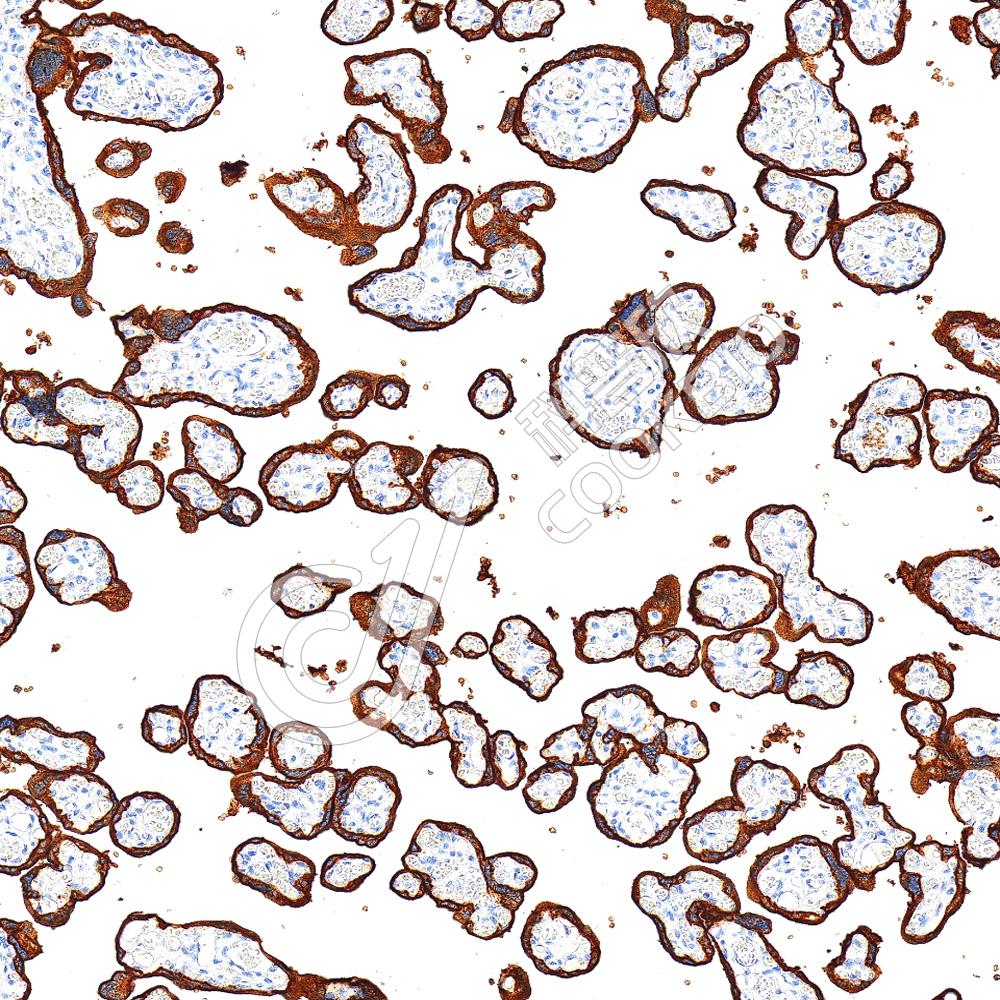

IHC检测CD21蛋白(货号 K5450363).

样品: 人扁桃体, 4%多聚甲醛 (货号KSG1101) 固定12-24小时.

抗原修复: Tris-EDTA抗原修复液(pH 9.0) (KSG1203), 100℃, 25分钟.

—抗: 1: 3500稀释, 4℃ 孵育过夜.

二抗: S-vision免疫组化多聚二抗(山羊抗兔),即用型 (货号KB3906), 室温孵育20分钟.

样品: 小鼠脾, 4%多聚甲醛 (货号KSG1101) 固定12-24小时.